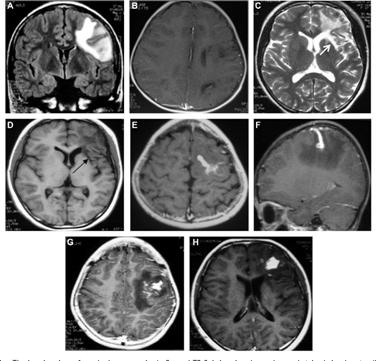

Bệnh ấu trùng sán nhái ở não (Cerebral sparganosis)

Thể bệnh này đặc trưng bởi các cơn động kinh cục bộ, lú lẫn, suy nhược, nhức đầu, giảm trí nhớ, hôn mê, sốt, dị cảm, yếu vận động, và một số triệu chứng khác ở thần kinh trung ương. Thể này thường liên quan đến một bán cầu não, đặc biệt thùy trán đỉnh (frontoparietal lobes), trong một số ca lan rộng đến tiểu não. Bệnh có thể gây nên xuất huyết não.

Nhiều nốt hình thành riêng rẽ dưới da có thể xuất hiện và biến mất theo thời gian. Các nốt thường ngứa, sưng phồng, đỏ lên và có di chuyển, thường kèm theo phù đau. Động kinh, co giật, dị cảm nửa thân mình và nhức đầu cũng là các triệu chứng thường gặp của bệnh sán nhái, đặc biệt bệnh sán nhái thể não và tăng bạch cầu ái toan cũng là dấu chứng cận lâm sàng hay thấy trên các ca như thế.

Hình 10-11. Một số thương tổn do sán nhái Spirometra spp. trên cơ quan thần kinh

Hình 12. Ấu trùng sán nhái gây thương tổn nhiều vị trí khác nhau trên nhu mô não

Xác định vị trí thương tổn bằng chụp cắt lớp vi tính (CT) hoặc chụp cộng hưởng từ (MRI) sẽ giúp cho chẩn đoán bệnh sán nhái tốt, nhất là thể sán não. Rạch và loại bỏ thương tổn và xác định loài sán để đưa ra chẩn đoán xác định. Trong trường hợp thể não, xét nghiệm ELISA dịch não tủy hoặc xét nghiệm huyết thanh sẽ giúp ích nhiều cho chẩn đoán, nhưng thường được khẳng định sau khi đã bắt được con sán. Chụp CT giúp hỗ trợ cho chẩn đoán lâm sàng, thường thương tổn có đặc điểm giảm âm, dãn não thất, các nốt bất thường, có nhiều vùng can xi hóa. Các chuyên gia khuyên nên chụp lại CT để đánh giá sự thay đổi kích thước cũng như vị trí tổn thương để chỉ định điều trị kịp thời nếu vẫn còn thương tổn.

CT và MRI đặc biệt hiệu quả trong chẩn đoán bệnh sán nhái ở não vì các hình ảnh thể hiện trong nhu mô não. Thông qua phân tích hồi cứu 25 ca sán trên não từ năm 2000-2006, tác giả Song và cộng sự tìm thấy một số đặc điểm có thể áp dụng như một khung chẩn đoán áp dụng trong tương lai mà không cần thực hiện sinh thiết hay phẩu tích mô thương tổn. Đặc điểm tìm thấy phổ biến nhất là dấu đường hầm ("tunnel sign") trên phim MRI cho thấy vết di chuyển của sán, trong khi đó hình ảnh thường thấy là hình tăng đavòng tròn hợp nhất, hay nhiều hình tràng hạt (thường là 3-6 vòng). Siêu âm tổng quát với nhiều loại đầu dò khác nhau cũng cho thấy có hữu ích trong chẩn đoán nhiễm trùng sán nhái trên các mô mềm và một số tạng.

Các nghiên cứu của Song còn đề nghị bổ sung với các dữ liệu về bệnh sử lâm sàng, xét nghiệm ELISA và hình ảnh của MRI hay CT scans đủ để chẩn đoán bệnh sán nhái. Tuy nhiên, các thương tổn này đôi khi dễ bị nhầm lẫn với thương tổn do lao. Trong một trường hợp sán nhái ở não không được chẩn đoán trong vòng 4 năm, khi chụp đã cho thấy chùm vòng tròn do chuyển từ bên phải sang bên trái của não, cuối cùng sán đã được tìm thấy qua sinh thiết.